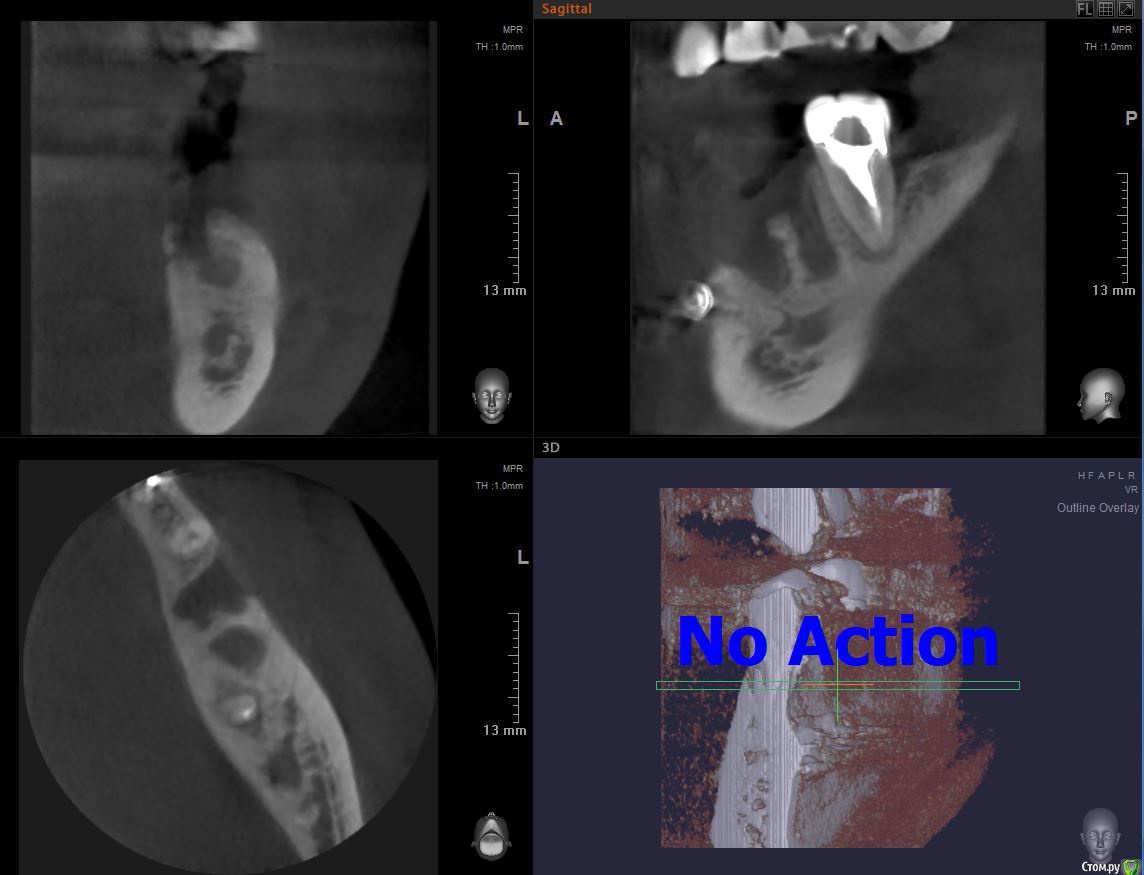

С  момента удаления прошло более двух месяцев, сегодня  сделал КТ.  Очень надеюсь, что я ошибаюсь, но выглядит так, как будто зуб удалили вчера. Кость не наросла или я что-то неправильно смотрю?

Здравствуйте! Кость есть,просто она ещё недостаточно минерализованна,потому плохо контрастируется на снимке. Имплант можно поставить в любых условиях. В вашем случае вероятно имеется дефект щёчной стенки гребня. Будет это препятствием для имплантации тли нет,зависит от доктора. В любом случае не мешало бы добавить объема мягким тканям(десне).

Если кому-то интересно, сегодня поставили имплант штрауман бон левел 4.8x8.

Кости как я понял не было, были остатки кисты и осколок от удаленного зуба.

Незаросшие лунки засыпали донорской костью, поставили мембрану.